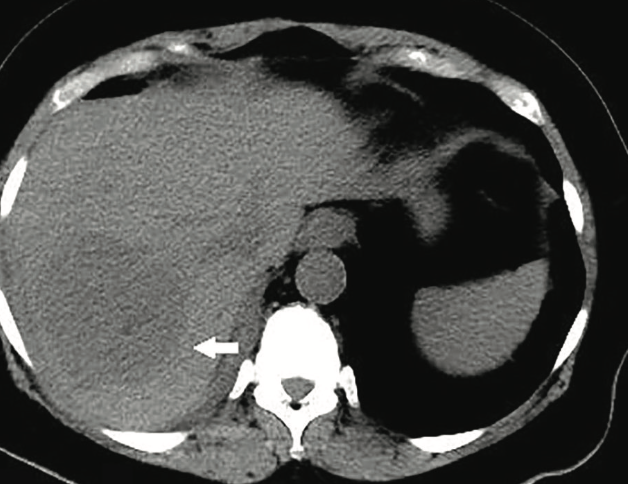

An 87-year-old man presented with a gradual onset of increased abdominal girth of 1 year’s duration. He reported that the associated symptoms had progressed to constant abdominal pain, fatigue, and...